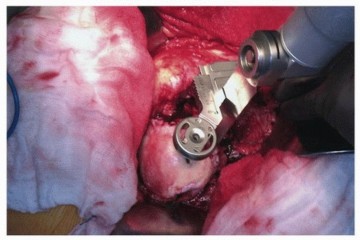

Proximal Preparation: Once the distal canal is prepared, a trial distal stem is inserted. Proximal preparation is then performed over the trial distal stem or a guide wire to ensure the proximal metaphysis is prepared coaxially with the distal diaphysis. Depending on the system, this involves sequential proximal milling or broaching. The proximal body size is selected to provide rotational stability and to fill the metaphyseal bone without causing cortical fracture.

Trialing and Assembly

With the distal trial and proximal trial body in place, trial necks and heads are applied. This is the critical juncture where the modularity is leveraged. The surgeon can independently rotate the proximal body or modular neck to set the femoral anteversion, independent of the distal stem's position in the diaphysis.

Taper Assembly: The assembly of the modular junction (whether mid-stem or neck-body) is the most technique-sensitive portion of the procedure. The male and female tapers must be meticulously cleaned of all blood, fat, and bone debris, and completely dried. Contamination of the Morse taper junction significantly increases the risk of mechanically assisted crevice corrosion and subsequent failure.

The proximal body is applied in the exact version determined during trialing. The components are engaged using the manufacturer-specific impaction tool. Multiple firm strikes with a heavy mallet are required to achieve cold welding of the Morse taper.